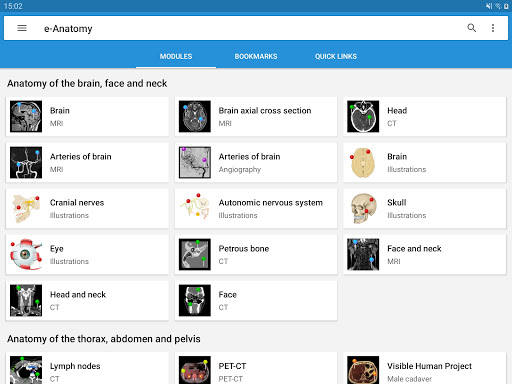

* تحسين التنقل في قائمة الوحدات النمطية مع وضع أفقي محسن على الهاتف المحمول

جديد: يمكنك الآن تصفية الوحدات حسب المنطقة أو نوع المحتوى حتى تتمكن من العثور على الوحدة التي تبحث عنها بشكل أسرع.

- وحدتان جديدتان: الدماغ - TOF والأوعية الدموية الدماغية ، أطلس التشريح الوعائي العصبي الطبيعي لشرايين الدماغ على الأوعية الدموية الدماغية. - تم إعادة صياغة الواجهة. - تتوفر علامة تبويب جديدة باسم "QuickLinks" ، ترسل وحدات في أقسام من جسم الإنسان وتسمح لك بالسفر السريع إلى الوحدات التي تبحث عنها. الخلل الصغيرة الثابتة.